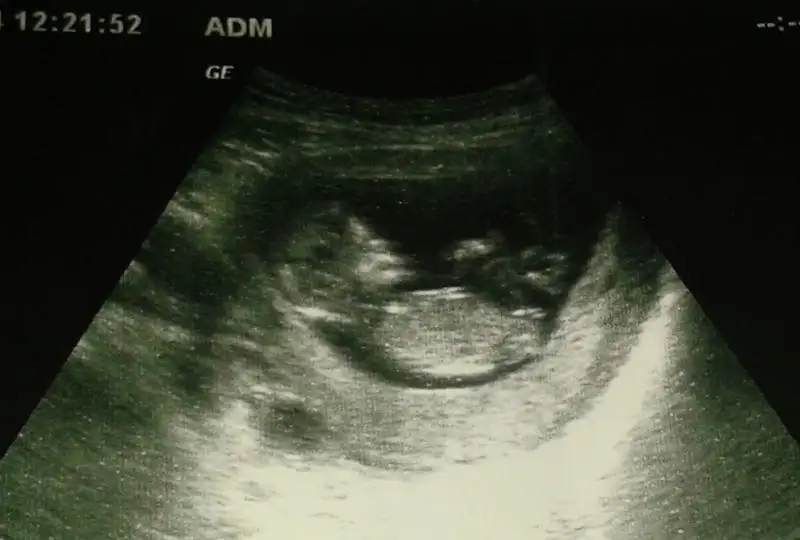

dr soylemeden siz gorun genital nub teorisi ( bebegin cinsiyeti)

merhaba. ben de burda o kadar çok yorum istedim ki bu konuda ama 1 kişi dışında yardıma alamadım. ben de resimleri inceleye inceleye fikir sahibi olmaya çalışıyorum. seninkini de eğer yanlış anlamadıysam şu linkte yorumlamaya çalıştım. umarım hakkında hayırlısı olur. Bana sanki kız gibi geldi. beyaz çizgi paralel gibi...

http://hizliresim.com/ydql3N